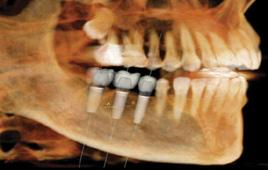

I am board certified in general and cardiothoracic surgery. Over the last few years I have refined my skills in minimally invasive surgery and most of the operations are performed robotically. Currently my scope of practice covers any chest pa thology including lung surgery, benign and malignant esophageal surgery among others surgeries in the chest.

Thoracic surgery is one of the most versatile specialties. I have particular interest in cutting edge technology such as robotic sur gery, navigational bronchoscopy and single incision surgery.

Lung surgery is the majority of my practice. I also perform surgeries in the esophagus; however, my scope of practice is very broad and in cludes surgery for reflux disease, thoracic outlet syndrome, surgery for diaphragmatic problems, chest wall reconstruction surgery and complex bronchoscopy and endoscopic procedures to mention few.

Medicine is an evolving field, you see so many innovations that can be overwhelming at times. In terms of surgery the technology with robotic surgery and minimally invasive techniques are very impres sive, however outside the OR we have seen the treatment of cancer change drastically. Radiation oncology, radiofrequency ablation and immunotherapy are just some of the innovations we see on regular basis.

Larry was referred to Dr. Luis Alberton, thoracic surgeon at Lo gan Health Medical Center. Dr. Alberton, one of the region’s most refined minimally invasive surgeons, assured Larry that robotic surgery would be the least invasive approach and would likely have a shorter recovery time. An avid outdoors man himself, Dr. Alberton understood the importance of a short recovery time for a person like Larry. Minimally invasive robotic surgery expedites a patient’s recovery time by avoid ing the chest wall trauma that would’ve been necessary for a more traditional thoracotomy.

In January 2022, three months after the bike accident, Dr. Alber ton performed a robotic lobectomy on Larry in which he removed about a quarter of his lung. Just two weeks after the procedure, Larry was able to resume some activities. And by the following summer, he was back biking Spencer Mountain. “I’m glad that I had somebody like Dr. Alberton taking care of me,” says Larry. “Tho racic surgery is a nice thing to have available in our community.”